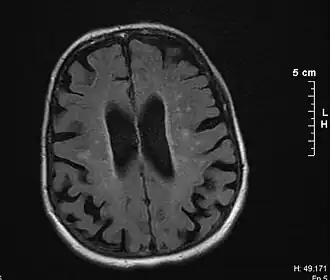

Cérebro de vítima de demência vascular por leucoaraiose

• Lesões extensas da substância branca (como por doença de Binswanger ou Leucoaraiose)